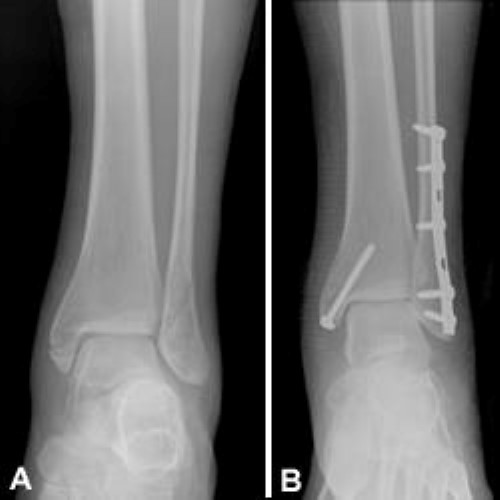

Ortho Blog Cmc Compendium from www.cmcedmasters.com This information will guide you through the next 6 weeks of your rehabilitation. Surgery on the medial malleoli can improve the chances of successful sometimes, a medial malleolus fracture may result in impaction of the ankle joint, which is when force often, a person will experience severe swelling around the fracture. A medial malleolar osteotomy is first performed, and is. Ing, and occasionally effusion at the medial portion. A medial malleolar fracture is corrected using large acutrak 2 4.7 screws. Medial malleolus fractures and fixation. Broke medial malleolus in two places 7 weeks ago. Treatment of these fractures often requires surgery.

Fractures of the medial malleolus usually occur in association with fractures of the lateral and, less commonly, posterior malleolus. Malleolar fractures include injuries of bones (malleoli) and or ligaments. What is a medial malleolus fracture? Please see the picture below to understand where this injury is. Marked soft tissue swelling over the lateral malleolus with a small bony fragment and increased lucency at the tip which is suspicious for an avulsion fracture. The medial malleolus indicates the lower end of the tibia. Isolated nondisplaced medial malleolus fracture or tip avulsions. Medial malleolus fractures and fixation. The most common symptoms of an ankle fracture are pain and swelling, either of which. Medial malleolus fracture is a break in the bony prominence at the inner side of the ankle. There is the medial malleolus with the deltoid complex (1) and the lateral common symptoms of a malleolar fracture are: Although a medial malleolus fracture can be a serious injury, the outlook for recovery is good, and complications are rare. Use the video or information below to gain a better understanding the swelling is often worse at the end of the day and elevating it will help.